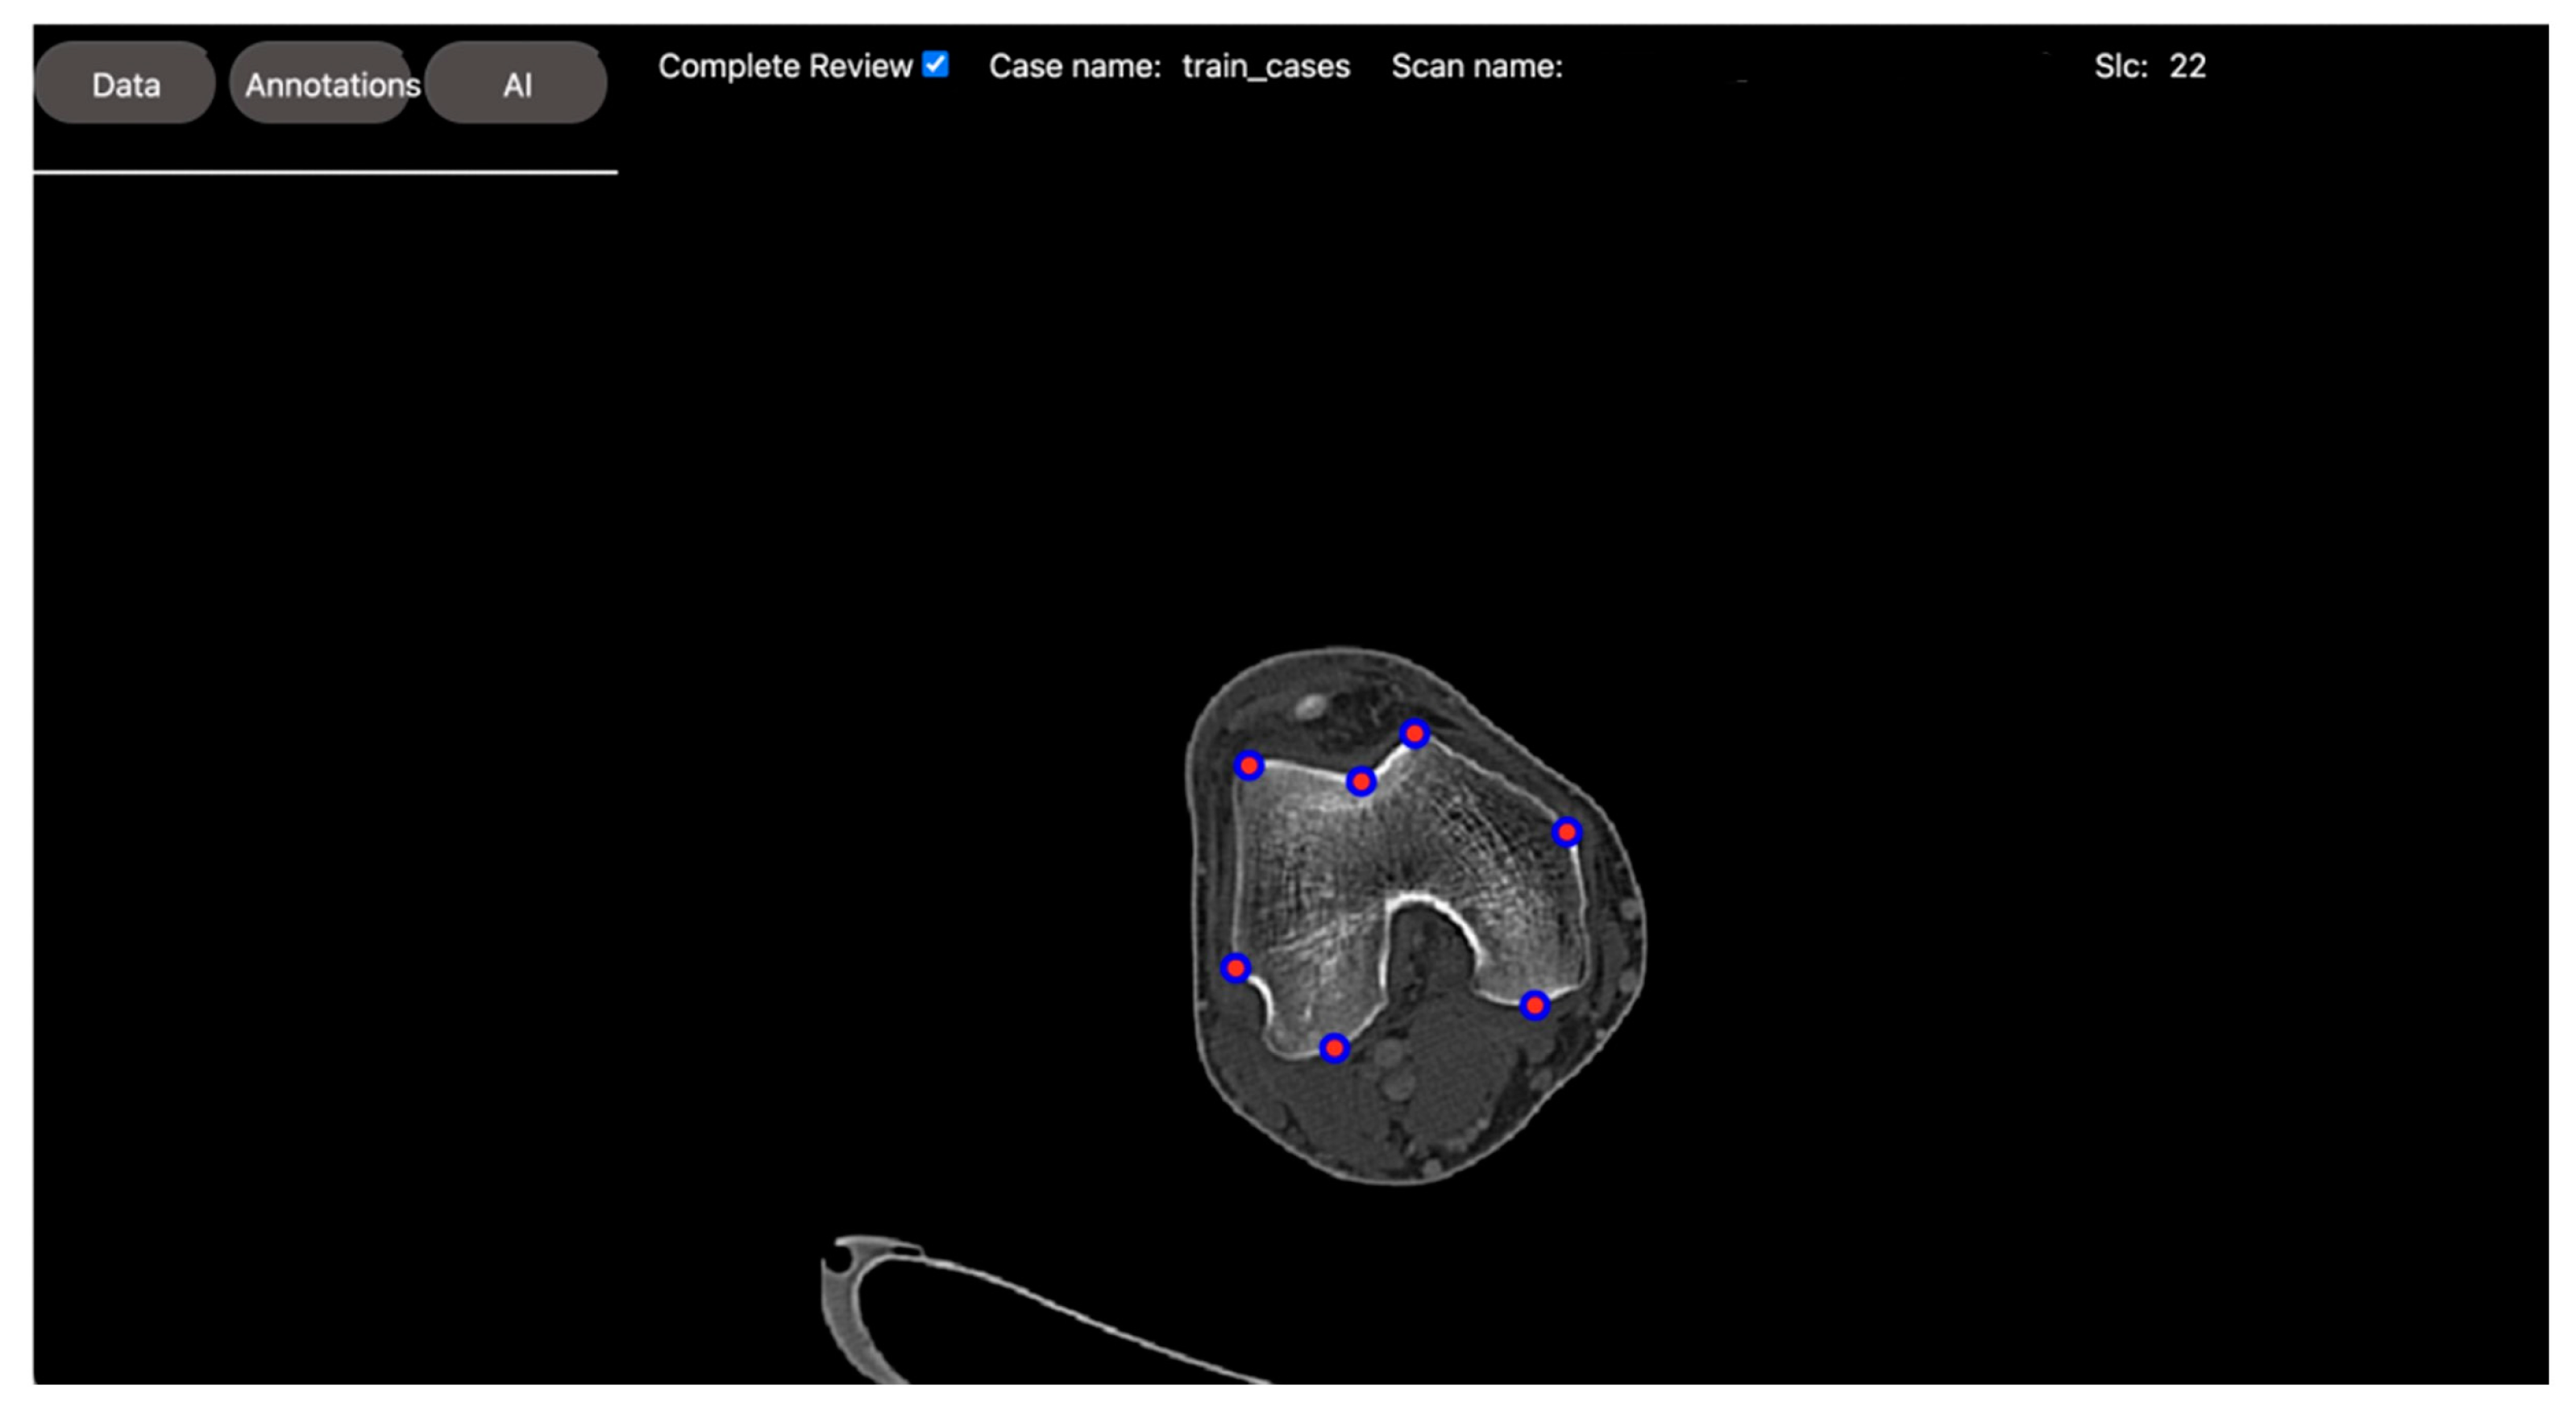

2.2.2. Regression Task: Automated Measurement of Patellofemoral Anatomic Landmarks

2.2.3. Classification Task: Normal vs. Osteoarthritis Knee Axial View CT Slice Classification